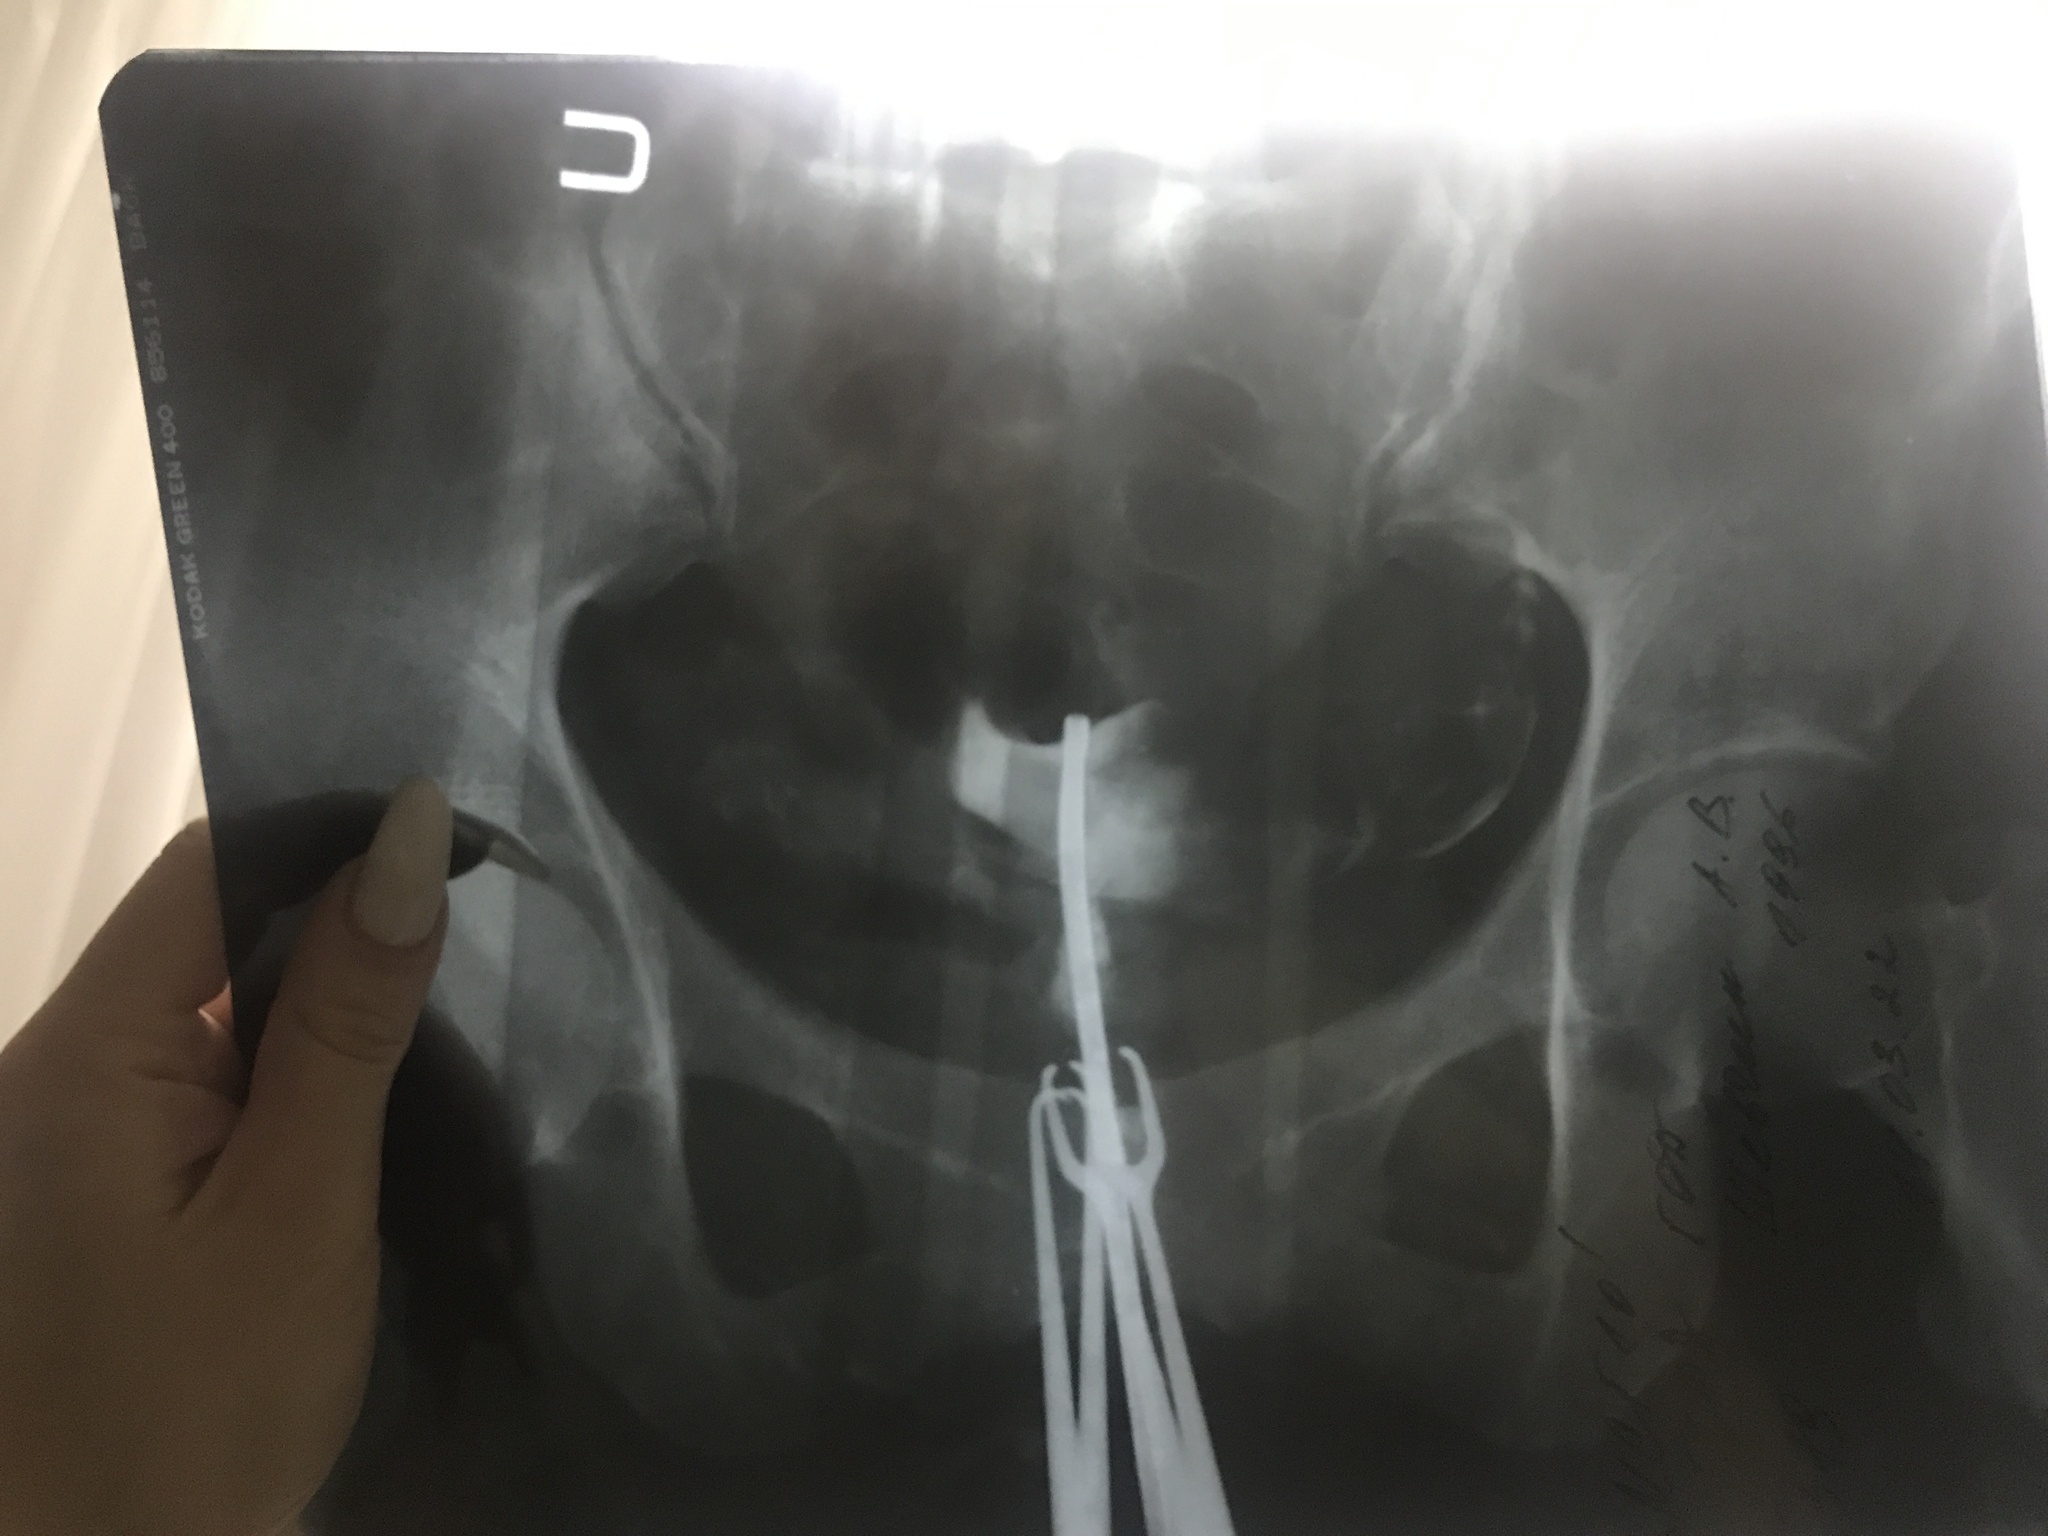

5. Рекомендуется проводить стимуляцию овуляции гонадотропинами или лапароскопию в качестве 2-й линии терапии при неэффективности кломифенцитрата или отсутствии условий для его применения - это к вопросу о дриллинге. Всё же, клинические рекомендации советуют нам для начала попробовать медикаментозные пляски с бубном. А вот при их неэффективности - уже развлекаться на хирургическом столе.

Рекомендуется проведение лапароскопии у женщин с СПКЯ и бесплодием при резистентности к кломифенцитрату, высоком уровне ЛГ, прочих показаниях к лапароскопической операции у пациенток с СПКЯ (эндометриоз, трубно-перитонеальный фактор бесплодия), невозможности мониторинга при использовании гонадотропинов.